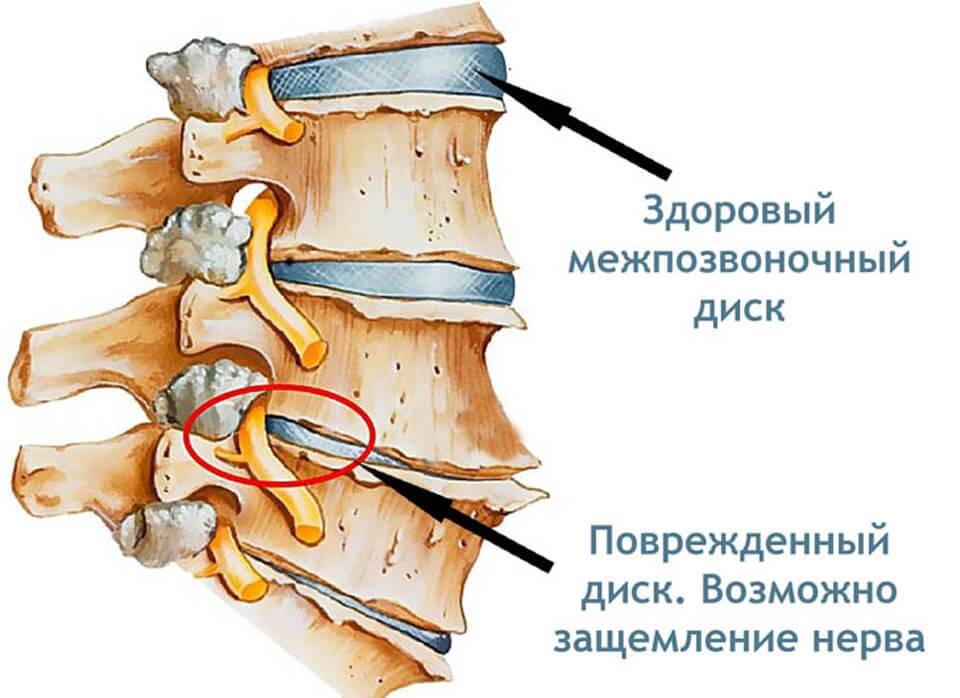

Структура позвоночника: сегменты и тазовые отделы в фотографиях